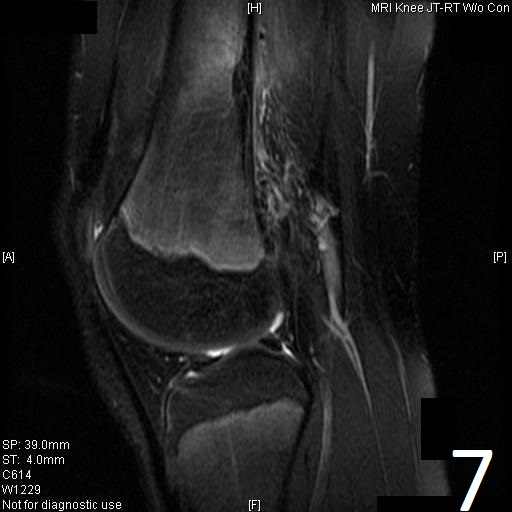

MRI

• Low- signal on T1 (Fig. 8)

• Variable heterogeneneous signal on T2 (Fig. 9).

• Possible extensive hypercellular fibrous tissue and hemosiderin seen on T2

• Can be useful for demonstrating an aneurysmal bone cyst component

Fig. 6-9: Sagittal T1 (Fig. 6) and T2 (Fig. 7) MRI of the knee demonstrates a fibrous cortical defect. Axial T1W (Fig. 8) and T2W (Fig. 9) show a heterogeneous lesion on distal femur, compatible with nonossifying fibroma.